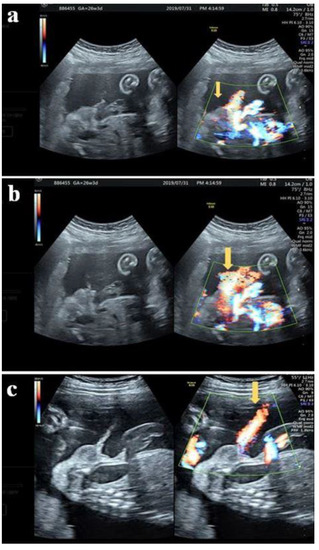

2.2. Case 2